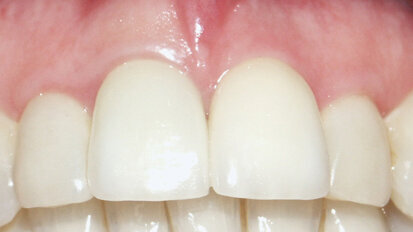

The patient pictured in Figure 1 was referred because the first clinician could not locate the canal(s). The patient had pain when chewing on #13 and mild ...